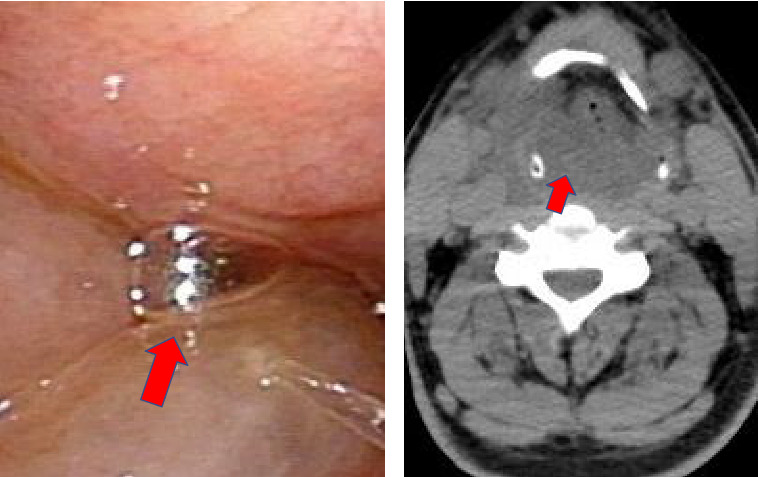

Relapsing epiglottitis has rarely been reported, and its etiology is not well established. A 44-year-old previously healthy Japanese man presented with a quickly progressing choking sensation. He had been experiencing refractory and relapsing laryngeal edema and probably acute epiglottitis (three episodes within 2 weeks), with rash and elevated pancreatic amylase. The patient required immediate intubation. After the initial extubation, he required reintubation and a subsequent tracheostomy. Antibiotics, glucocorticoid, and antihistamines were administered, and he finally recovered with the tracheostomy's closure. Potential causes of this patient's relapsing epiglottitis are as follows: persistent right swollen tonsil; a positive result on a Mycoplasma pneumoniae antigen test and a particle agglutination (PA) test, implicating chronic tonsillitis; and/or Mycoplasma infection. This is the first case report of refractory and relapsing epiglottitis requiring reintubation possibly concurrent with chronic tonsillitis and Mycoplasma infection.